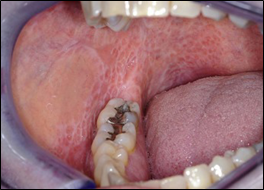

Proliferative verrucous leukoplakia (PVL)

Aggressive form of oral leukoplakia. Most patients with PVL, occurs more frequently on the gingiva20 (Figure 3).